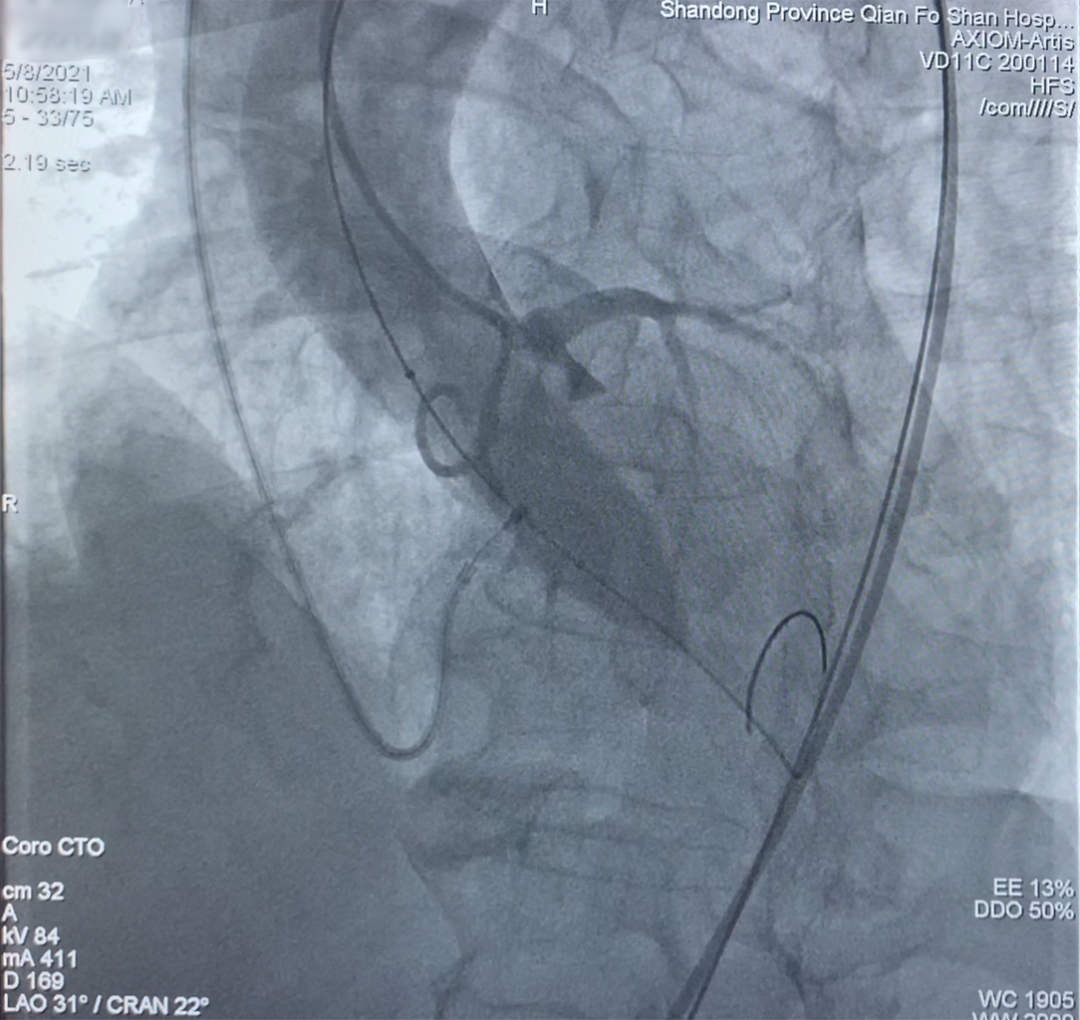

1. 使用20mm球囊跨瓣后进行预扩张,窦底造影显示球囊膨胀完全,冠脉显影通畅,无瓣周漏。

2. 迅速送入Vitaflow27mm人工瓣膜至主动脉瓣释放位置,尝试调整人工瓣膜与主动脉瓣同轴,进行释放。